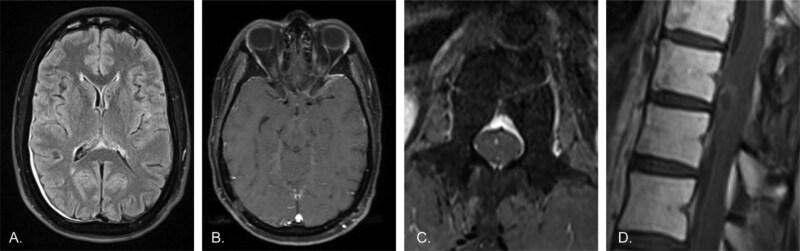

CASE PRESENTATION

A previously-healthy 33 year old man was diagnosed with DL-GNT, which harbored a pathogenic BRAF:KIAA1549 gene fusion. He was initially treated with a MEK inhibitor but developed drug-related cardiotoxicity. Without treatment, he developed significant functional limitations due to leptomeningeal disease. A compassionate use indication was pursued for an investigational CNS-penetrant type II BRAF inhibitor, tovorafenib. Within 3 months of initiating the medication, the patient experienced notable gains in functional status and with over 12 months of treatment has been able to rejoin recreational activities.

病例介绍

一名既往健康的33岁男性被诊断为DL-GNT,其携带致病性BRAF:KIAA1549基因融合。他最初接受MEK抑制剂治疗,但出现了药物相关的心脏毒性。未经治疗,由于软脑膜疾病,他出现了明显的功能受限。为一种研究性的可穿透中枢神经系统的II型BRAF抑制剂托伐拉芬尼申请了同情用药。在开始用药的3个月内,患者的功能状态有显著改善,经过超过12个月的治疗,他已能够重新参加娱乐活动。